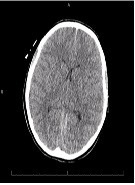

Cerebral Edema Treated Successfully after Liver Transplant in a Patient with Acute Iron Toxicity

Fariha Hussain, Tuba Rashid Khan, Pallav Bhattarai*, Lakshmi Raman